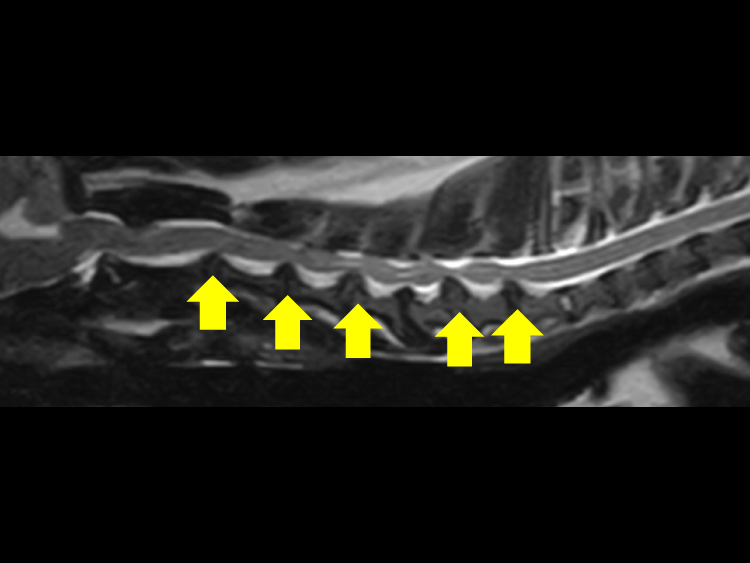

チワワなどの小型犬で最近多い疾患で首の骨に多発する椎間板ヘルニアがあります。

従来はベントラルスロットという手術が適応でしたが多発性の場合は適応は難しいです。

その場合は背側からアプローチして椎弓を切除することができます。一つ穴で手術ができます。

切開創は一箇所で複数の椎弓を切除することが可能な手技になります。